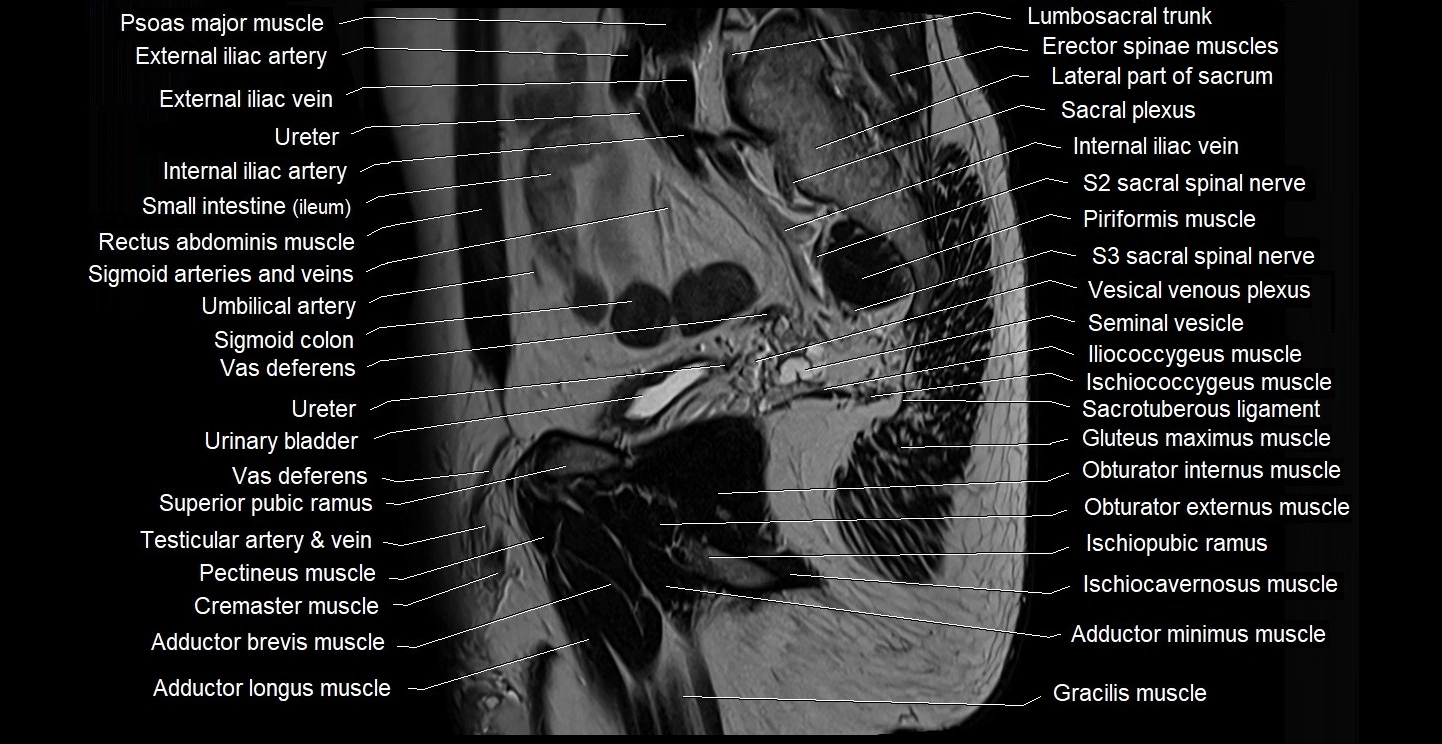

- Erector spinae muscles

- Internal iliac artery

- Internal iliac vein

- Lumbosacral trunk

- Piriformis muscle

- Psoas major muscle

- Rectum

- Sacral plexus

- Seminal vesicle

- Sigmoid colon

- Urinary bladder

- Vas deferens